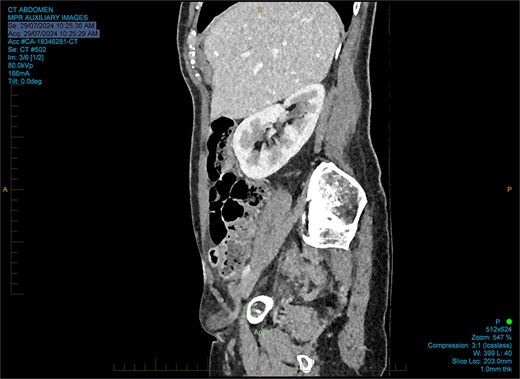

She had normal inflammatory markers and lactate. A computed tomography (CT) scan was reported as a direct right inguinal hernia containing the appendiceal tip (an Amyand’s hernia). There was adjacent soft tissue density and fat stranding raising the possibility of incarceration (Figs 1 and 2).

The working radiological diagnosis was an incarcerated Amyand’s hernia. However on examination, the lump appeared to be below the inguinal ligament more in keeping with a femoral hernia. Therefore under general anaesthesia, a high approach was taken. This revealed a femoral hernia under the inguinal ligament. Rectus sheath was opened transversely. A preperitoneal reduction was unsuccessful so peritoneum was opened in the right iliac fossa. This revealed an appendix incarcerated in the femoral hernia. The hernia was reduced revealing a grossly inflamed appendiceal tip (Fig. 3). An open appendicectomy was done, the hernia was closed with an intraperitoneal 1–0 Ethibond suture before closing the peritoneum, fascia, and skin.